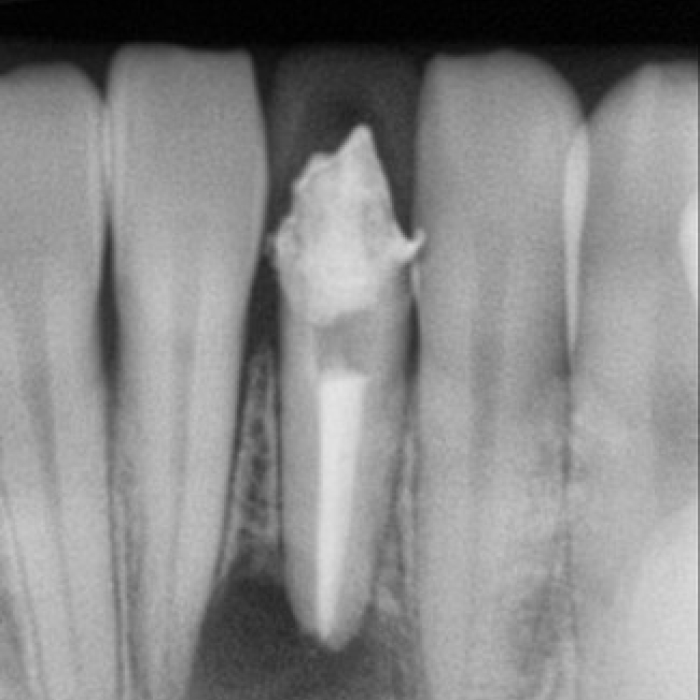

신경치료 전후 사례

• 치료전

치료후